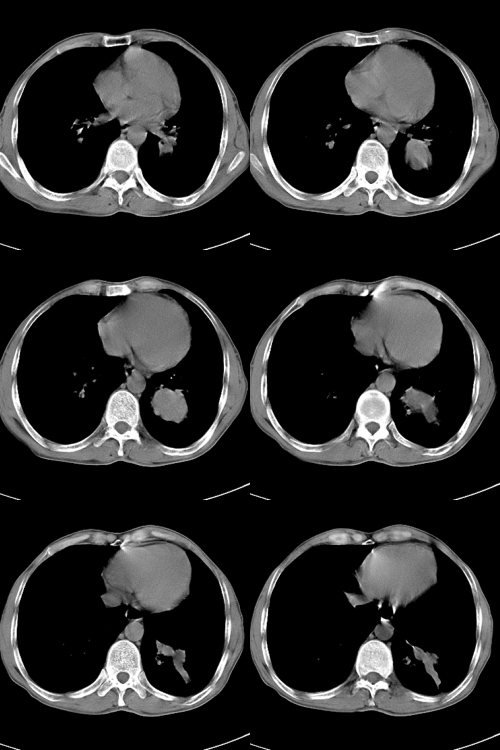

以下是引用zsl6918在2009-2-7 7:38:00的发言:[br]恶性度极高的肺癌,肺门及纵隔淋巴结转移。

以下是引用余辉在2009-2-7 8:29:00的发言:[br]考虑左下肺周围型肺癌伴肺门、纵隔淋巴转移及右肺转移